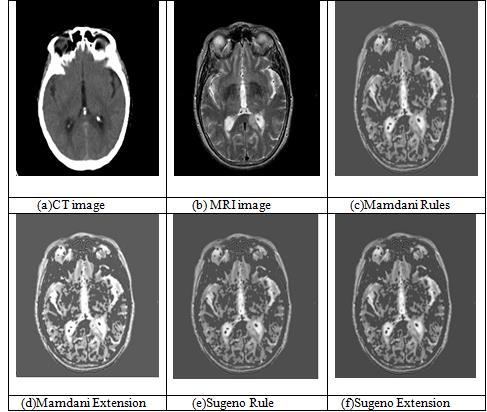

The fusion results of set two CT and MRI images are displayed in Figure 4. The CT input picture is picture (a), whiletheMRIinputimageisImage(b).Thefusedpictures from the Mamdani rules are shown in Image(c), while the fusedimagesfromtheMamdaniextensionmethodareshown inImage(d).Itisobviousfrompictures(c)and(d)thatthe fusedimageproducedbyMamdanirulesissubstantiallyless

clear than the one generated by Mamdani extension. The fusedimageobtainedfromtheSugenoextensionmethodis Image(f),whilethefusedimageobtainedfromtheSugeno rulesisImage(e).Ithasbeendemonstratedbythephotos(e) and (f) that the fused image produced by the Sugeno extension is significantly superior to the output image producedbytheSugenorules.

Table1aboveliststheobjectivemetricsforthesecondbatch of CT and MRI images. Here, calculations are made for entropy,mutualinformation,andedge-basedqualitymetrics. The entropy values for Mamdani and Sugeno are same. In contrast to Mamdani FIS, Sugeno FIS improvises Mutual Informationvalues.MamdaniandSugenorulesbothhavethe same Edge Based Quality Metric values, yet Mamdani has higher(QAB/F)valuesthanSugeno.